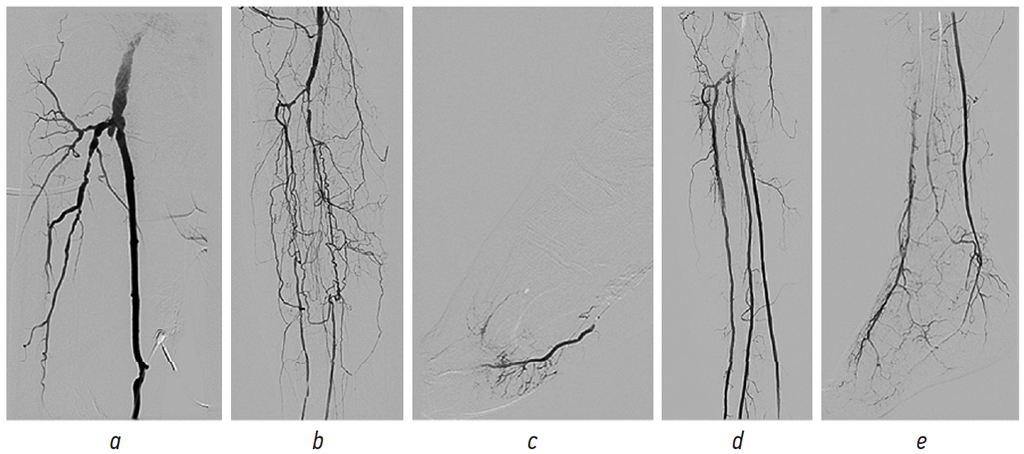

Эндоваскулярные вмешательства в группе ДГВ выполняли после БПШ — либо в тот же день непосредственно после зашивания ран (симультанные ДГВ), либо спустя несколько дней (двухэтапные ДГВ) (см. рисунок).

Рис. 1. Пример симультанного дистального гибридного вмешательства, выполненного пациенту 64 лет с критической ишемией нижних конечностей и глубокими трофическими изменениями в бассейне латеральной плантарной артерии: a — интродьюсер 6F установлен антеградно через боковую ветвь функционирующего бедренно-подколенного шунтирования; b — селективная прямая ангиография артерий подколенно-тибиального сегмента через интродьюсер: окклюзия всех трех артерий голени; с — этап реканализации задней большеберцовой артерии: инъекция контрастного вещества в латеральную плантарную артерию через просвет баллонного катетера; d — окончательный результат эндоваскулярного вмешательства: все три артерии голени функционируют; e — прямая ангиосомная реваскуляризация стопы

Симультанный подход использовали в тех случаях, когда трофические изменения на пораженной конечности носили глубокий и стремительно прогрессирующий характер. В два этапа вмешательство проводили у пациентов с поверхностными и непрогрессирующими некротическими изменениями. Временной интервал между БПШ и эндоваскулярной коррекцией путей оттока составлял 2–10 дней. Перед операцией все пациенты ежедневно получали АСК в дозе 100 мг/сут. При симультанных ДГВ пациенты принимали нагрузочную дозу клопидогрела (300 мг) непосредственно после завершения открытого этапа реконструкции с целью снижения возможной кровопотери во время шунтирования. При двухэтапных ДГВ нагрузочную дозу клопидогрела назначали непосредственно перед вторым (эндоваскулярным) этапом вмешательства. В качестве внутрисосудистого доступа использовали антеградный бедренный, контрлатеральный бедренный либо боковую ветвь аутовенозного шунта. Выбор доступа осуществлял оперирующий хирург. Чаще всего использовали интродьюсер 6French. Перед началом реканализации пораженного артериального сегмента пациенту внутривенно вводили нефракционированный гепарин в дозе 5000 МЕ. Реканализацию окклюзирующих поражений в подколенном сегменте проводили с помощью гидрофильного проводника диаметром 0,035 дюйма, в тибиальном сегменте — с помощью гидрофильного проводника диаметром 0,014 дюйма. После выхода проводника в истинный просвет дистальнее окклюзии в зону поражения по проводнику устанавливали баллонный катетер (в ряде случаев для облегчения антеградного продвижения катетера требовались короткие инфляции баллона), затем выполняли баллонную ангиопластику при номинальном давлении, продолжительность ангиопластики составляла 90 с после полного расправления баллона. Если после первой инфляции баллона ангиографический результат был неудовлетворительным (остаточный стеноз >30 % либо гемодинамически значимая диссекция), проводили повторную инфляцию под давлением на 2 атм выше номинального продолжительностью 120 с. Если и после этого сохранялся остаточный стеноз/диссекция, в зону ангиопластики имплантировали самораскрывающийся стент без лекарственного покрытия (в подколенном сегменте) или баллон-расширяемый стент, покрытый паклитакселом (в тибиальном сегменте).